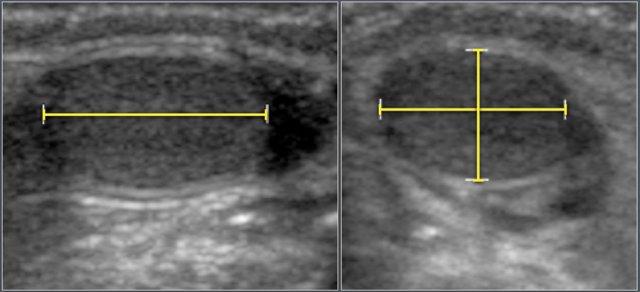

Các số đo siêu âm được thu thập từ 344 bé trai thuộc nhiều dân tộc khác nhau.

Thể tích tinh hoàn được tính theo công thức:

Chiều dài × Chiều rộng × Chiều cao × 0,523